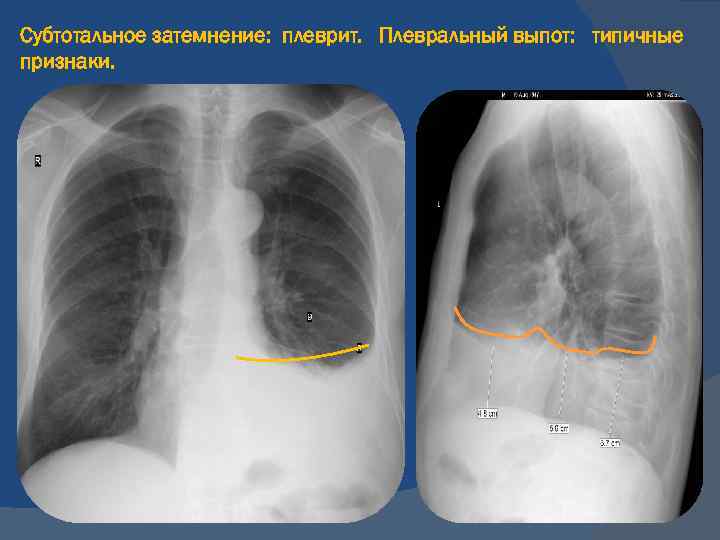

Диагностика плеврального выпота: что нужно знать